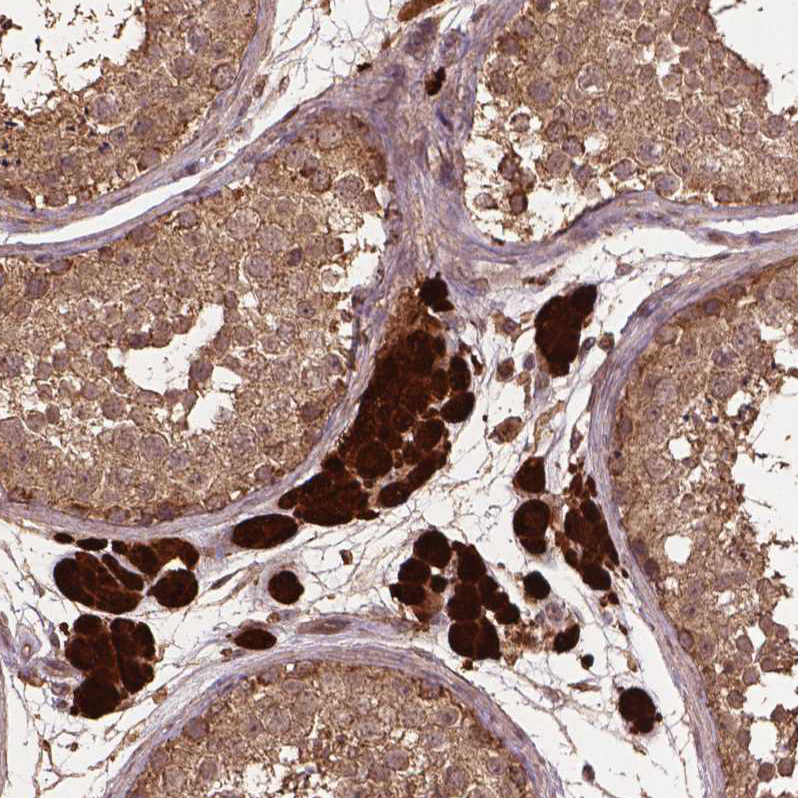

Immunohistochemical staining of human testis shows strong cytoplasmic positivity in Leydig cells.